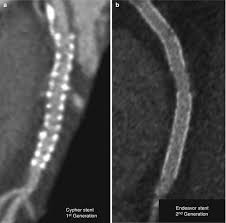

Evaluation Of Soft Plaque Stenoses In Coronary Artery Stents Using Conventional And Monoenergetic Images First In Vitro Experience And Comparison Of Two Different Dual Energy Techniques Hickethier Quantitative Imaging In Medicine And Surgery

Evaluation Of Soft Plaque Stenoses In Coronary Artery Stents Using Conventional And Monoenergetic Images First In Vitro Experience And Comparison Of Two Different Dual Energy Techniques Hickethier Quantitative Imaging In Medicine And Surgery from cdn.amegroups.cn